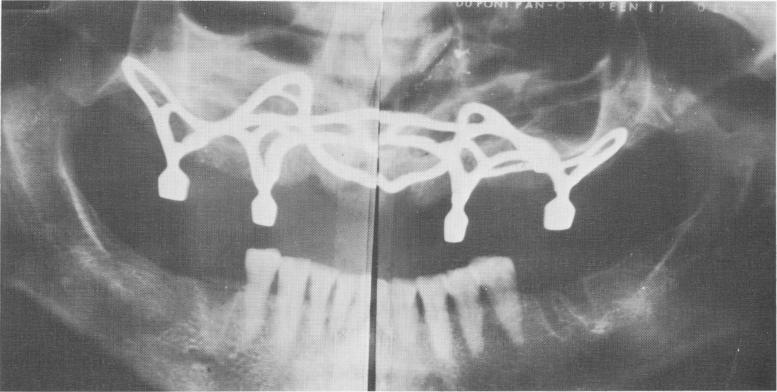

Fig. 12-84. A Panorex x-ray of the subperiosteal implant shows the topography of the bone that it covers. This implant should have been contraindicated because it opposed natural teeth.

1 Maxillary subperiosteal implant shows topography of bone that it covers